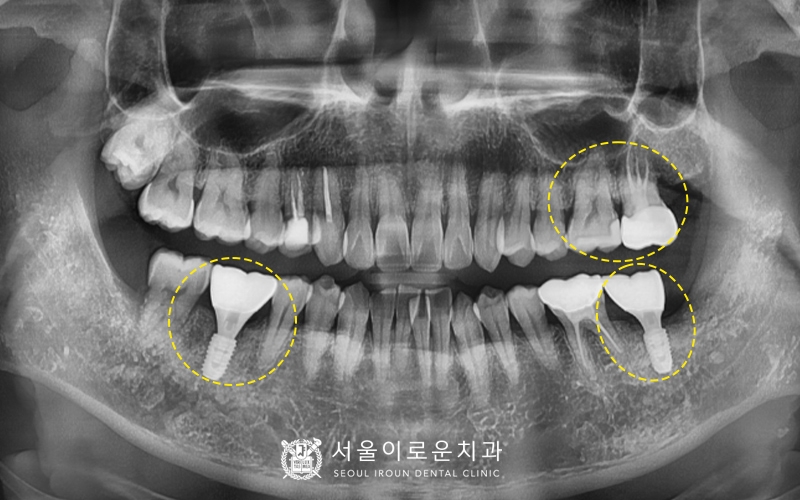

모든치료가 마무리된 뒤

촬영한 x-ray 입니다!

환.자분은 전반적인 통증이 사라지셔서

만족해하셨고

수술도 통증없이 잘 받으셔서

만족해하셨습니다. 🤗

처음 부천서울이로운치과로 내원하셨을 때와 비교하면

양쪽 아래 큰 어금니(#37,46)가

파절되어 제 기능을 하지 못하였는데

현재 임플란트를 통해 저작력을

보완할 수 있게 되었습니다~!

🦷치료 전>후🦷

또한, 통증이 있어 불편하셨던

왼쪽 위 큰어금니와 앞에 있던 치아는

각각 필요한 다른 치료를

진행함으로써 이를 뽑지 않고

치아보존을 위해 노력하였습니다. 😁